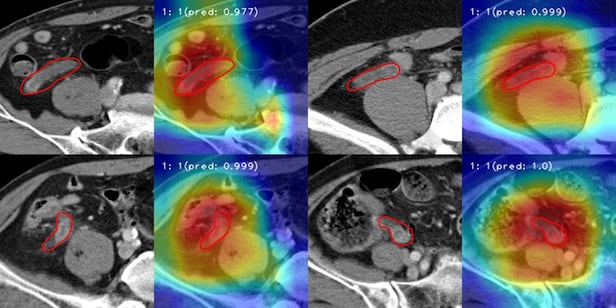

AI(인공지능)가 CT(컴퓨터단층촬영) 영상을 실시간으로 관찰해 충수염을 진단하고 있다. 붉은색 실선은 AI가 충수 부위를 집중적으로 관찰하며 충수염 여부를 확인하고 있는 모습. /한림대병원

한림대성심병원 연구팀이 개발한 AI 모델은 CT 영상을 실시간으로 관찰해 충수염만 진단하는 게 가능하다. 대장염, 말단회장염, 상행결장게실염 등 충수염과 임상적으로 유사한 질환을 걸러내는 것이다.

이후 충수염 환자 1839명, 충수염이 아닌 것으로 진단받은 1782명의 데이터를 걸러내고 '3D 콘볼루션 신경망(CNN)'을 활용한 모델에 학습시켰다. 학습을 마친 AI 모델의 충수염 진단 정확도는 89.4%로 나타났다. AI 모델의 성능을 평가하는 데 사용하는 '곡선하면적(AUC)' 점수는 0.890으로 집계됐다.